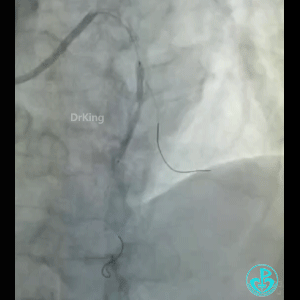

急性前壁心梗,两小时。

导丝怎么扩真怪!急性心梗前降支导丝通过顺利,球囊扩张后导丝移位很多!不在原来的血管腔!_https://www.jmylbn.com_新闻资讯_第1张

怎么解释导丝和血管的关系?

BMW导丝,预扩前导丝是弯曲的,预扩时球囊也是弯曲的,预扩后导丝拉直,血管的弯曲还在。